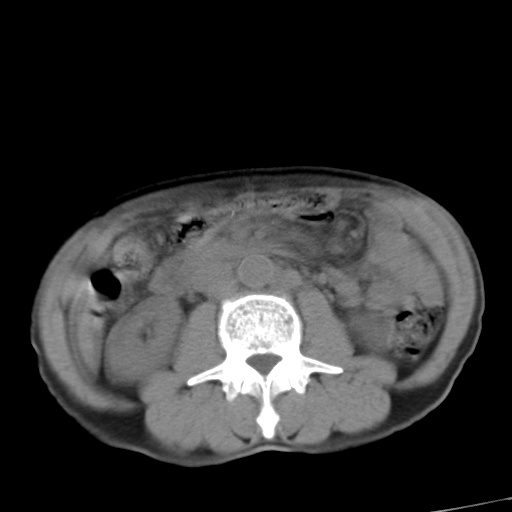

考虑胃癌并肝脏及腹膜后淋巴结转移;不排除淋巴瘤。

肝内转移瘤,腹腔及腹膜后淋巴结转移。